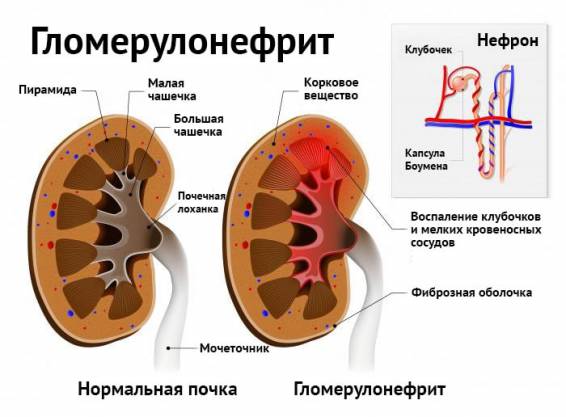

Механизм остро го диффузного гломерулонефрита